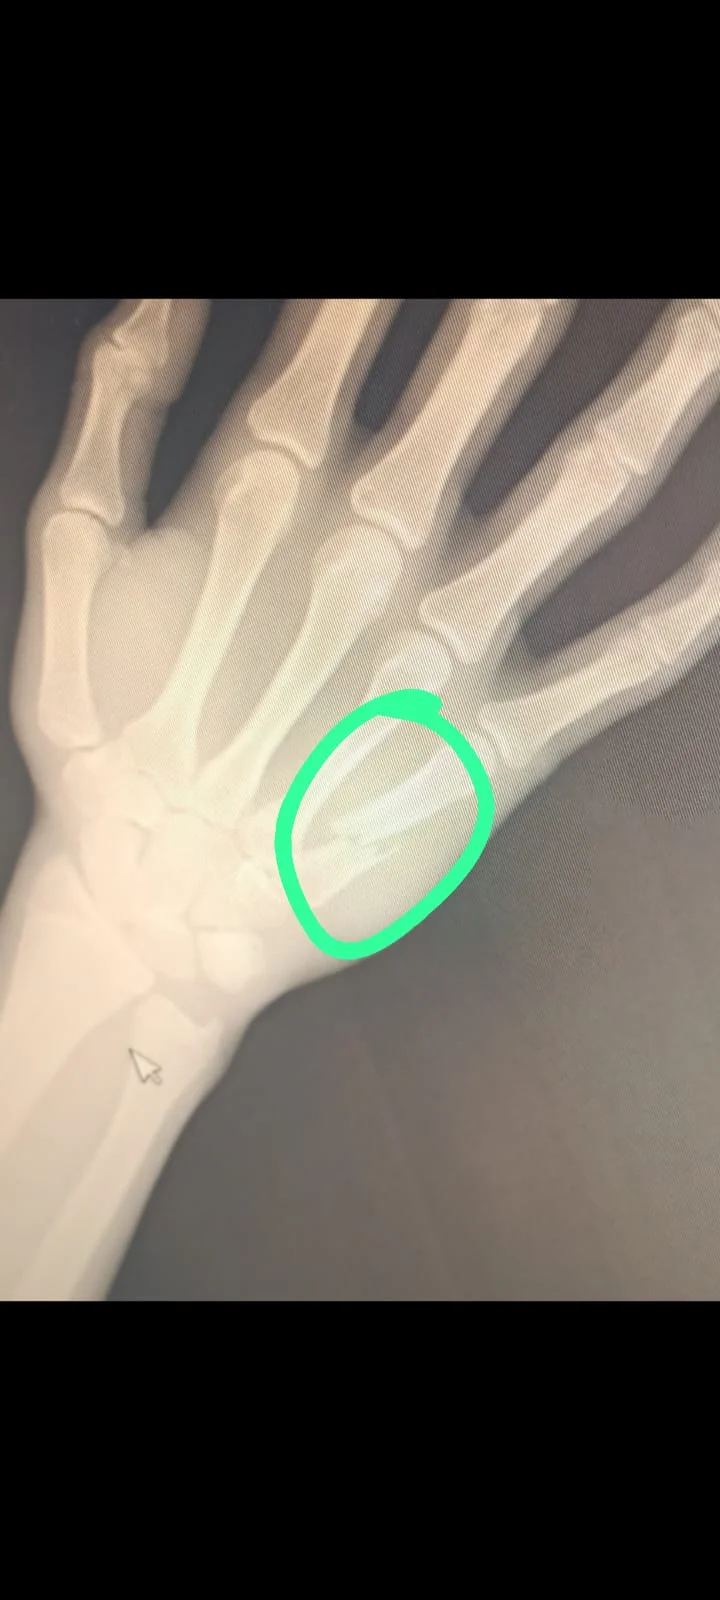

15 yaşındayım babam beni korkutuyor askere falan gidemezsin diye. Çok kötü bir şey bu polis falanda olamam o zaman. Çok fazla valorant oynuyordum ama artık kemik kırık olduğu için oynayamıyorum. Tamamen iyileştiğimde oyunda daha mı kötü olurum? Elim kaç aya iyileşir acaba? Ameliyat durumuda var bu arada.

Boksör kırığı genelde Knuckle denilen yerdir ya da burundur.

Senin kemik normal sakarlık sakatlığı. O kemik ise ameliyat olmadan düzelmez ve ara ara ağrı yapar. Ama ne olursa olsun askerliğe ya da polisliğe engel olmaz.

Yapma ya umarım öyle olmaz şuan herhangi bir ağrısı yok. Birde ameliyat olursak elimizin içine platin falan takıyorlarmı?

Orası belki normal kaynayabilir belki platin takarlar. Platin taksalar bile büyük ihtimalle ufak bir şey takarlar. Onun da askerliğe engeli yok. Askerlik için kafanı yormana gerek yok yani, sen tedavini ol.